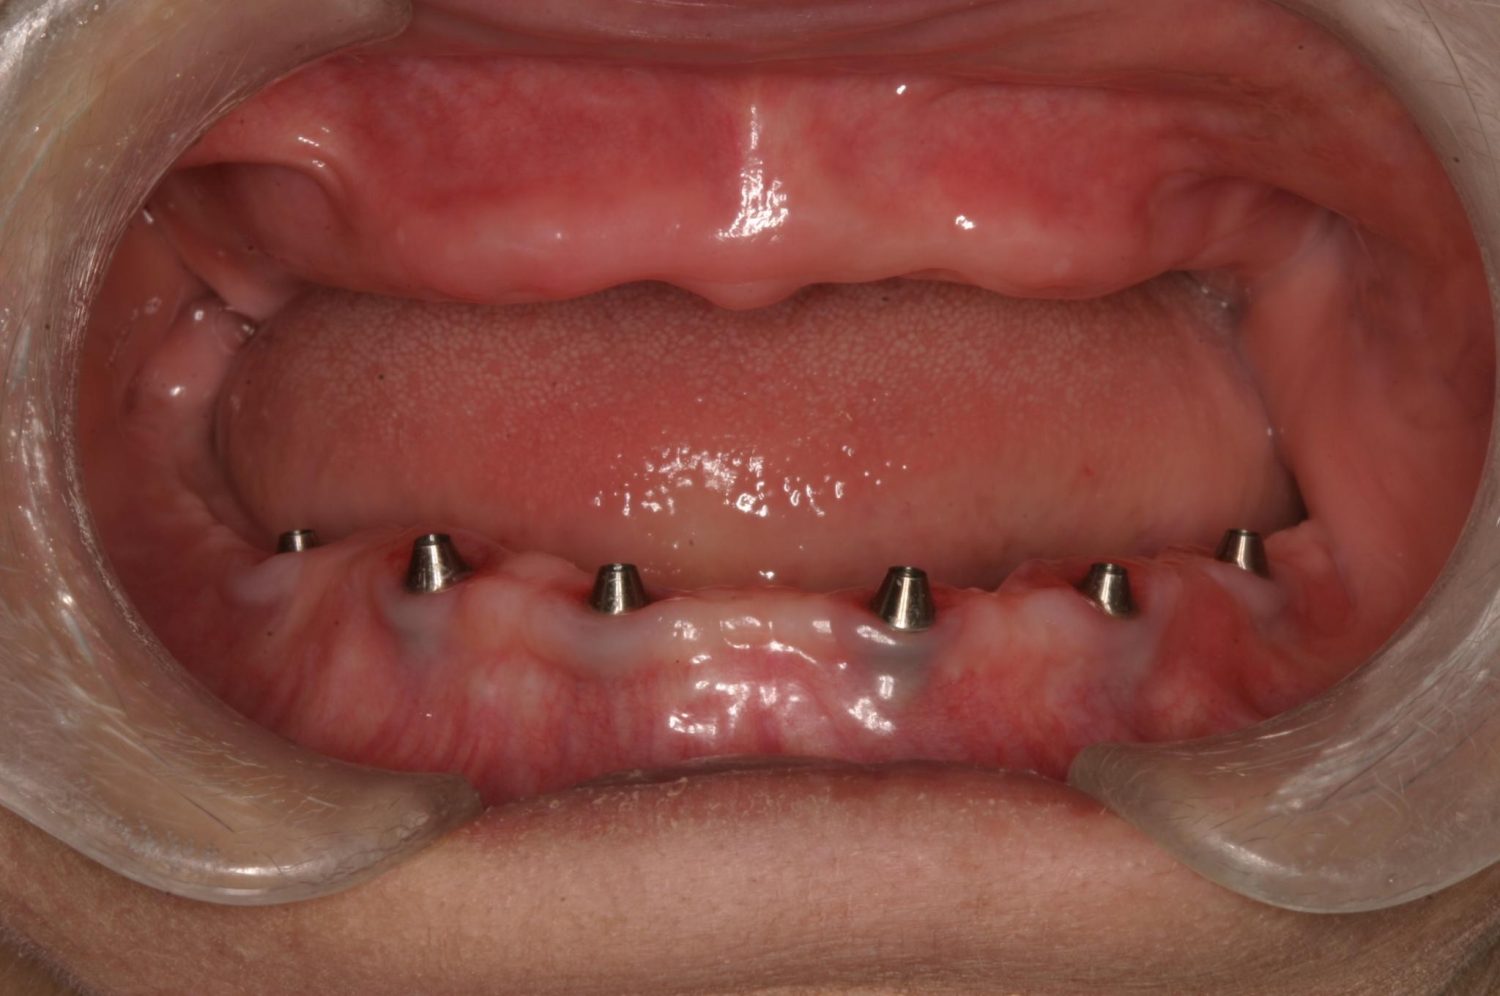

インプラント治療の症例紹介③

Before

After

主訴

むし歯の治療

治療内容

保存不可能な歯の抜歯

下顎にインプラント埋入し咬合再構成

治療費

2,688,400円(税込)

治療期間

14か月

治療回数

21回

想定されたリスク

※上部構造の形態が複雑になるため清掃が難しくなる。インプラント周囲炎の恐れがありました。

多数歯う蝕および多数歯欠損による咬合崩壊、保存不可能な歯の抜歯により上下無歯顎に。下顎に6本インプラント埋入する事で咬合再構成を行った。